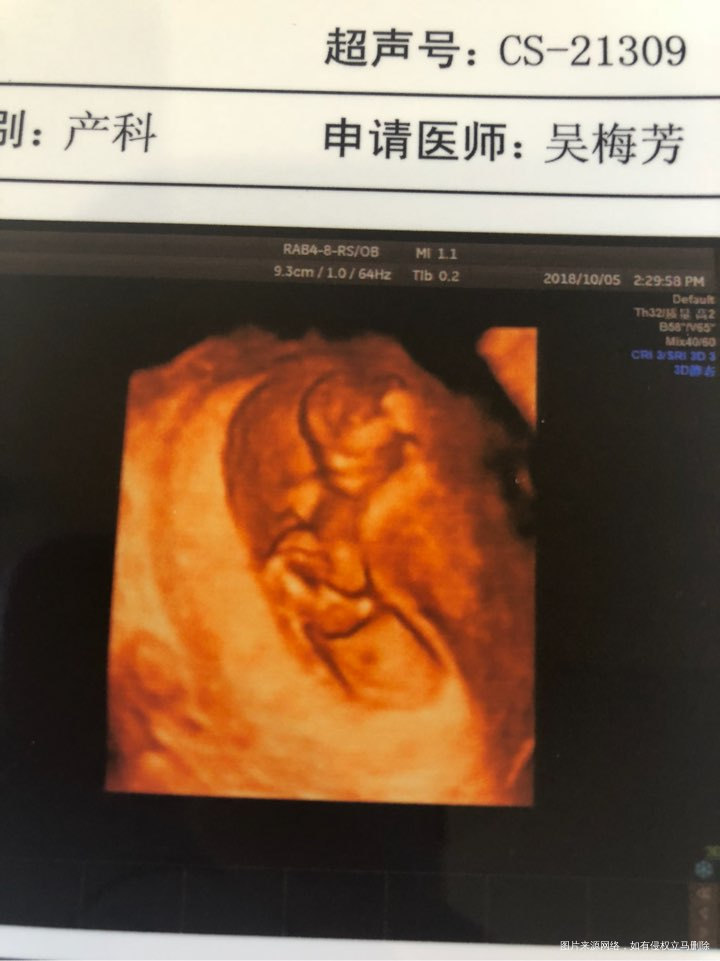

嘿嘿 抓怕到你坐着了

好像看见小鸡鸡